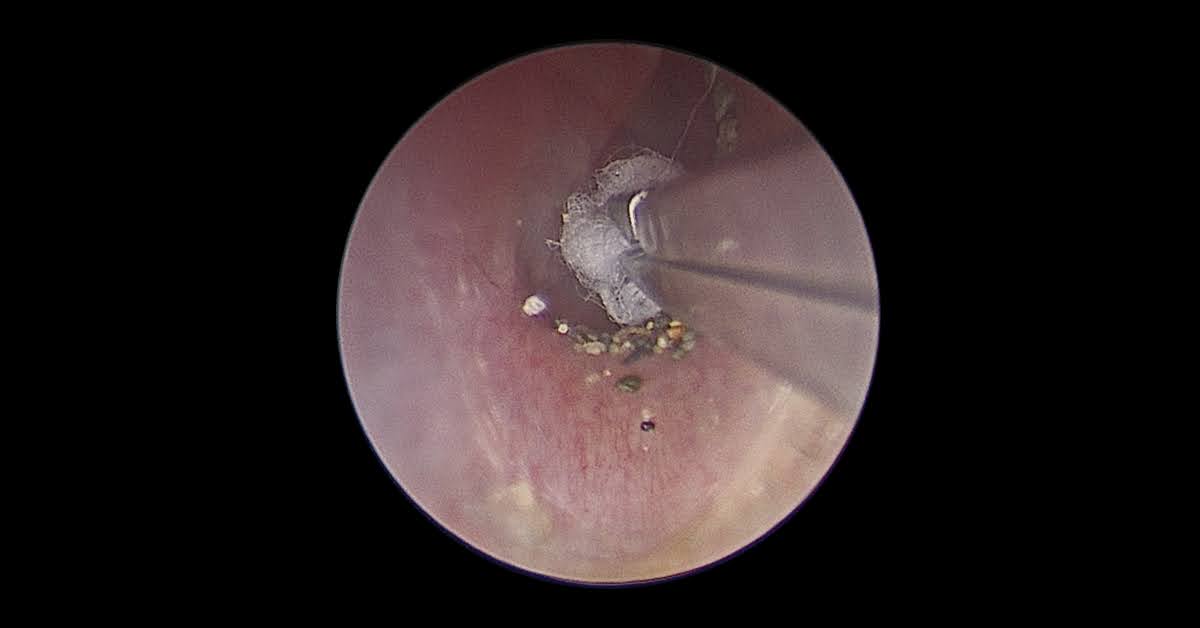

(患者到海邊遊玩,不小心耳朵進沙,耳內視鏡下將細小的沙子看得十分清楚)

(內視鏡下取出沙子)